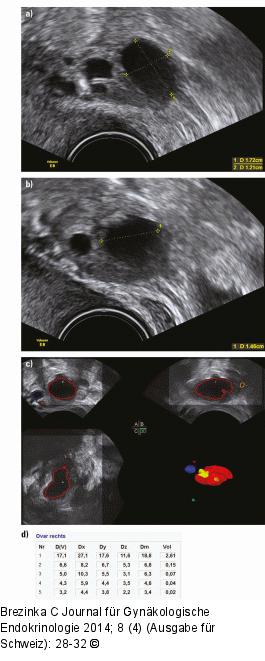

Abbildung 3a-d: Follikelmessung 11. Zyklustag bei Low-dose-Stimulation: (a) Zunächst wird der Follikel in der maximalen Größe dargestellt und gemessen, (b) in der Folge wird der Schallkopf 90° gedreht und eine weitere Messung durchgeführt. (c) Die Sono-AVC-Messung zeigt den größten Follikel in Rot an. (d) Die Messung zeigt zuerst den auf die elliptische Form des Follikels bezogenen Follikeldurchmesser D(V), dann die Messung in 3 Ebenen, wie sie das System vornimmt, und dann den Mittelwert aus Dx, Dy und Dz. Der letzte Wert gibt das errechnete Volumen in Millilitern an. |

11. Zyklustag bei Low-dose-Stimulation: (a) Zunächst wird der Follikel in der maximalen Größe dargestellt und gemessen, (b) in der Folge wird der Schallkopf 90° gedreht und eine weitere Messung durchgeführt. (c) Die Sono-AVC-Messung zeigt den größten Follikel in Rot an. (d) Die Messung zeigt zuerst den auf die elliptische Form des Follikels bezogenen Follikeldurchmesser D(V), dann die Messung in 3 Ebenen, wie sie das System vornimmt, und dann den Mittelwert aus Dx, Dy und Dz. Der letzte Wert gibt das errechnete Volumen in Millilitern an. |